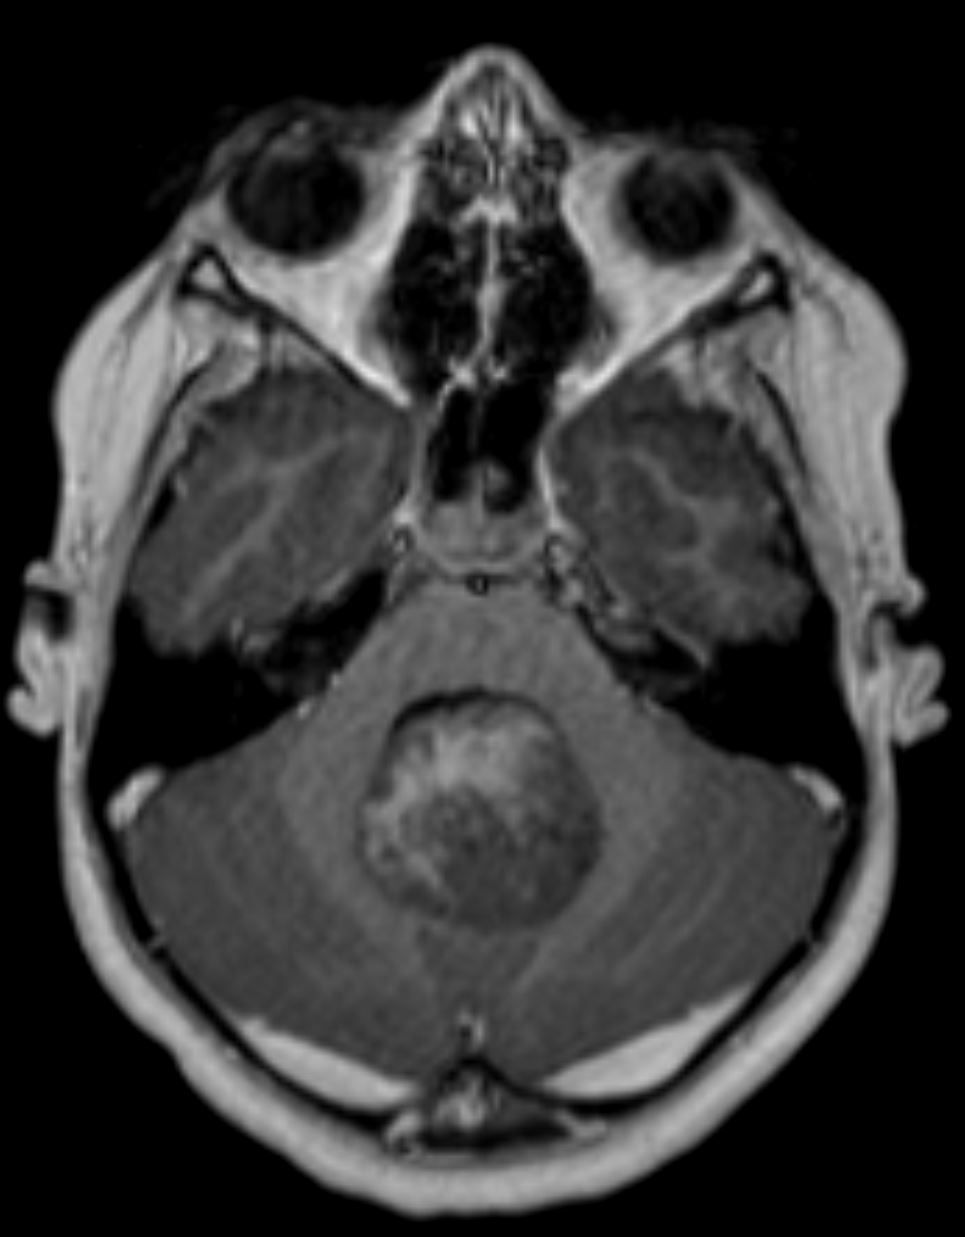

Image IQ Quiz: Pediatric Patient Presents with Double Vision

Pediatric patient presents with double vision. What is the most likely diagnosis?